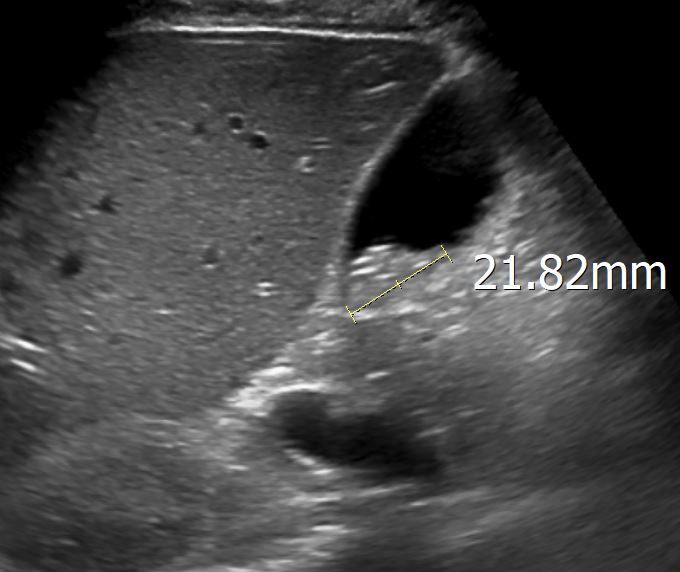

소노그래퍼 선생님은 자세에 따른 움직임과 신호를 근거로 슬러지(결석)이라고 의견 주신다는데 저는 영상에서 음영이 나타나지 않아 암은 아닐까 너무 걱정 됩니다.

간은 이상 없고 췌장 body duct 2.3mm check

GB Polyp 다수 발견되었고 가장 큰 건 9mm입니다.

초음파 사진을 두 장만 봐서는 판단이 어렵긴 합니다만, 체위 변경에 따른 움직임을 실시간으로 확인했다면 작은 돌이나 슬러지일 가능성이 높습니다.

다만 담석은 담낭 용종과 함께 발견된 경우 수술의 적응증이 되므로 수술이 가능한 병원에서 담낭절제술에 대한 상담도 함께 받으시는 것이 좋겠습니다.